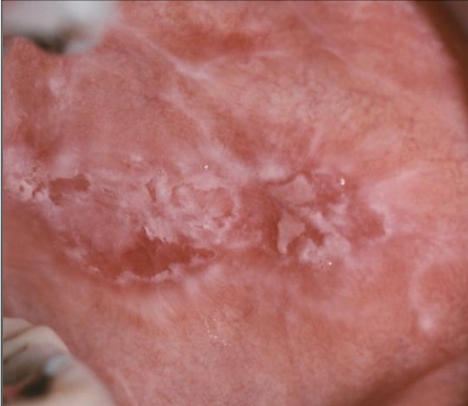

What is reticular lichen planus?

More common, asymptomatic, lace-like (Wickham striae)

White lace-like striations (Wickham striae), maybe erythematous, bleeding

Buccal mucosa, gingiva, tongue, lip